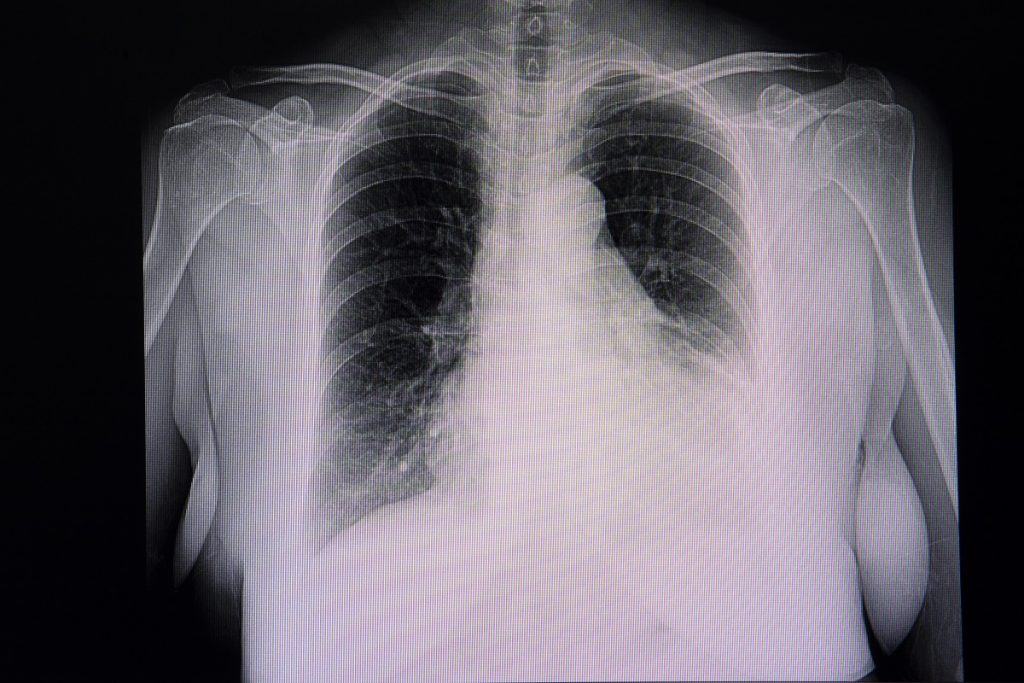

- Radiographie thoracique de face : elle suffit lors des gros épanchements.

On réalisera alors une radiographie thoracique de contrôle post ponction systématiquement à la recherche de la complication la plus fréquente : pneumothorax iatrogène causé par l’aiguille de ponction.